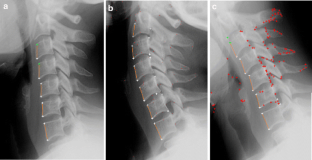

This study was conducted to evaluate a new method used to calculate vertebra orientation in medical x-ray images. The goal of this work is to develop an x-ray image segmentation approach used to identify the location and the orientation of the cervical vertebrae in medical images. We propose a method for localization of vertebrae by extracting the anterior—left—faces of vertebra contours. This approach is based on automatic corner points of interest detection. For this task, we use the Harris corner detector. The final goal is to determine vertebral motion induced by their movement between two or several positions. The proposed system proceeds in several phases as follows: (a) image acquisition, (b) corner detection, (c) extracting of the corners belonging to vertebra left sides, (d) global estimation of the spine curvature, and (e) anterior face vertebra detection.

Fig 4